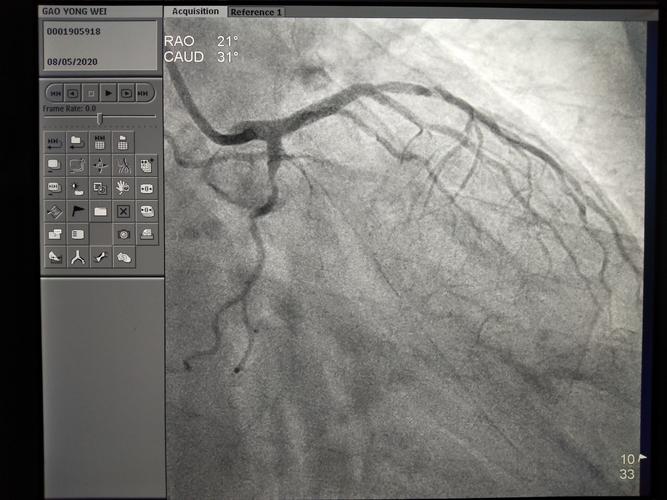

今天下午冠脉造影示lcx 可疑om 2近端100%闭塞,但无法判断断端.

冠状动脉造影 观察lad,lcx起始部,lcx全程,钝缘支(om) 全程 右前斜